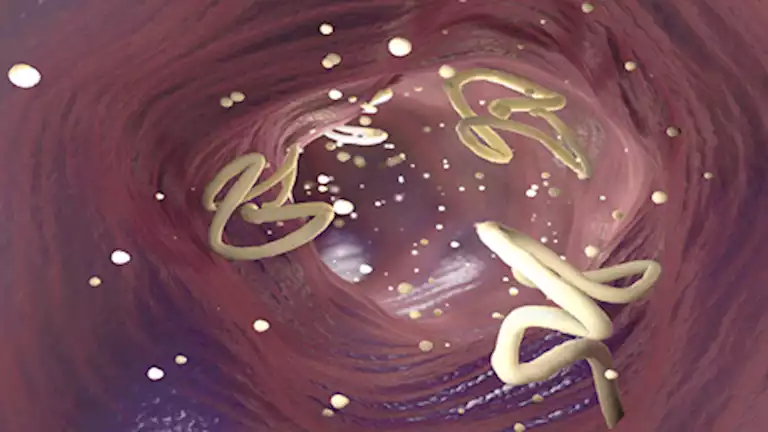

أصيب رجل بحالة من الفزع بعدما اكتشف أن جسده مليء بأكياس دودة شريطية، حيث أظهرت الأشعة السينية عقيدات تشبه “حبوب الأرز”، التي تبين أنها أكياس ناتجة عن عدوى طفيلية.

وأوضح غالي أن المريض، الذي لم يتم الكشف عن هويته، أصيب بهذا المرض بسبب تناول لحم خنزير نيئ أو غير مطبوخ بشكل كافٍ يحتوي على يرقات دودة شريطية، التي تلتصق بأنسجة الجسم وتكوّن أكياسًا قد تتناثر وتسبب العدوى.

وقال غالي في مقطع فيديو انتشر بشكل واسع: “الأكياس موجودة في كل مكان، ومن الصعب حتى حسابها”. وأوضح أن هذه الأكياس يمكن أن تنتقل إلى مناطق مختلفة في الجسم، وفي حالة هذا المريض، كانت تتركز الأكياس في الأنسجة الرخوة للوركين والساقين.

وذكر أن هذه العدوى، المعروفة بداء الشريطيات (الشريطية الوحيدة)، تحدث بعد تناول بيض الدودة الشريطية الموجود في لحم خنزير ملوث أو غير مطبوخ جيدًا. وتسبب الأكياس النسيجية مرض داء الكيسات المذنبة، الذي يشكل خطورة كبيرة، خاصة إذا أصاب الدماغ أو الجهاز العصبي، وهو ما يُعرف بداء الكيسات المذنبة العصبي.